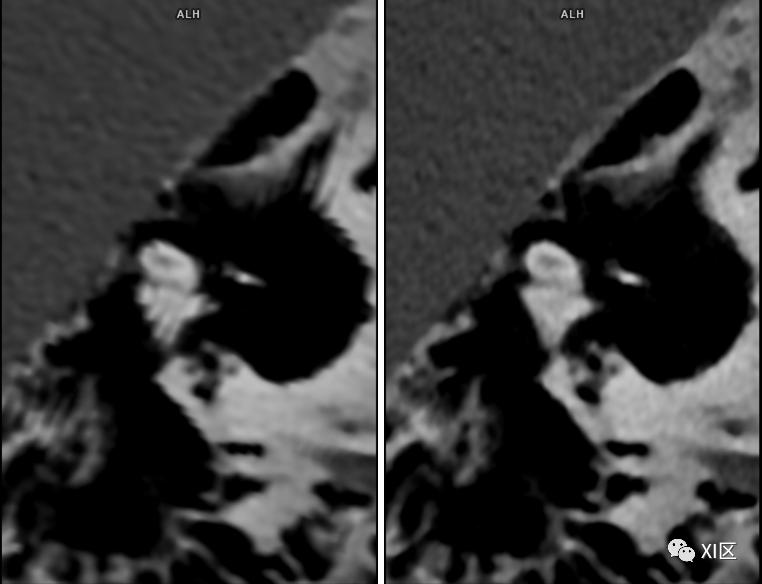

SOMATOM Force CT常规扫描重建0.6 mm(192x0.6 mm)图像(左)与IVR重建0.6 mm(576x0.6 mm)图像(右)比较。使用IVR技术的图像内耳细微结构显示更清晰。